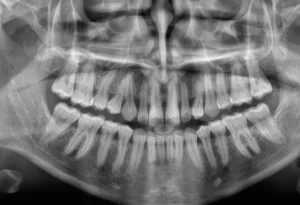

Para recibir tu formulario online tienes dos opciones muy sencillas. Mediante WhatsApp o mediante el formulario de consulta enviándonos vuestras fotos y radiografías.

Envíanos tus fotos y radiografías, nuestro equipo de profesionales la analizará y se pondrá en contacto

Envíanos tus fotos y radiografías